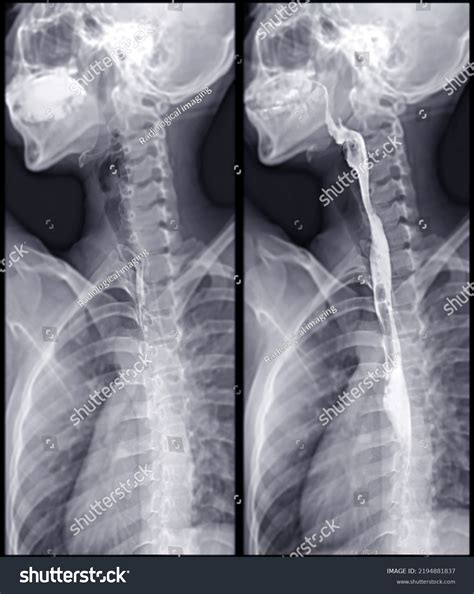

A Barium Swallow Test is essentially a "movie" rather than a snapshot. While standard X-rays provide a static image of your bones or lungs, this test utilizes a technique called fluoroscopy, which allows the radiologist to watch the barium move in real-time as you swallow. This dynamic view is crucial for identifying exactly where a blockage or dysfunction might be occurring during the act of deglutition (swallowing).

The barium sulfate used in the procedure acts as a contrast medium. Because it is radio-opaque, it shows up bright white on X-ray images, effectively "painting" the walls of your throat and esophagus. This makes it possible to visualize conditions such as:

- You will be instructed to swallow the liquid while the radiologist watches the screen. They may ask you to swallow at different speeds or in different positions, such as lying flat or tilted.